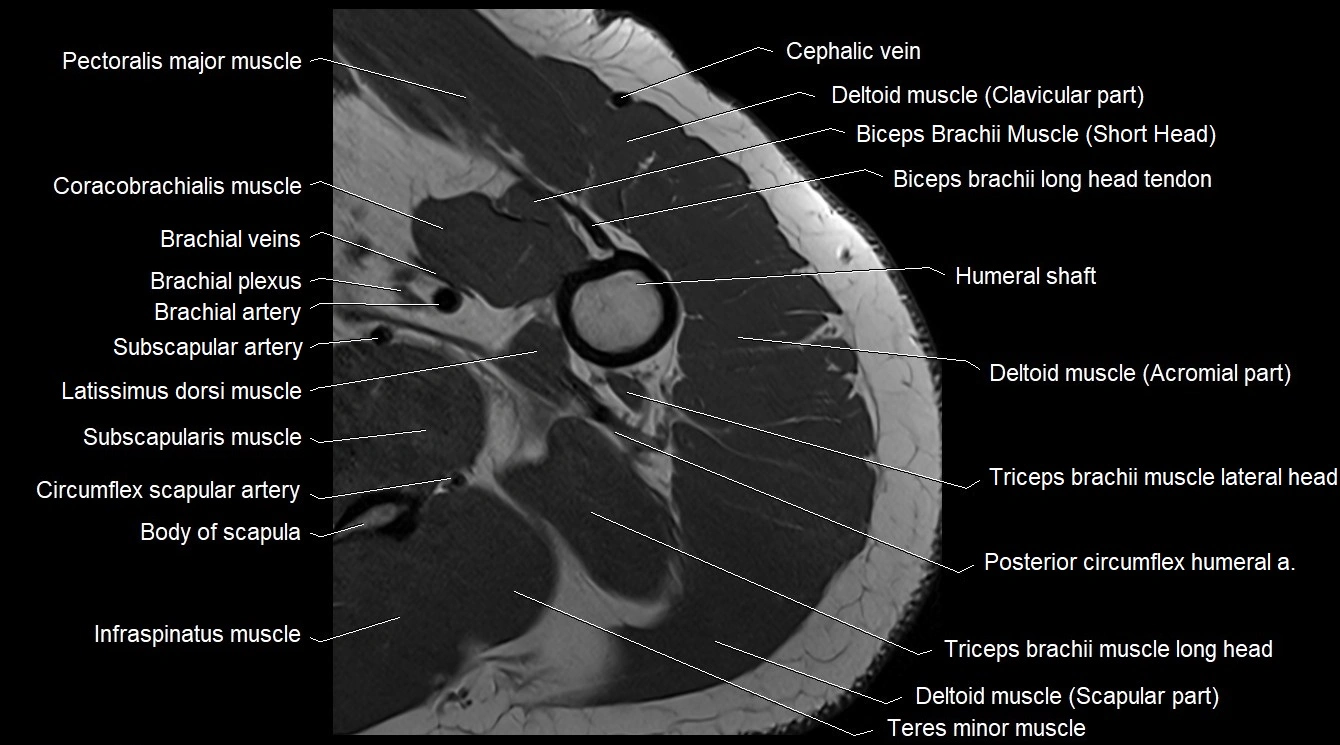

- Pectoralis major muscle

- Coracobrachialis muscle

- Brachial artery

- Subscapularis muscle

- Deltoid muscle

- Infraspinatus muscle

- Teres minor muscle

- Teres major muscle

- Triceps brachii muscle

- Long head of triceps brachii muscle

- Lateral head of triceps brachii muscle